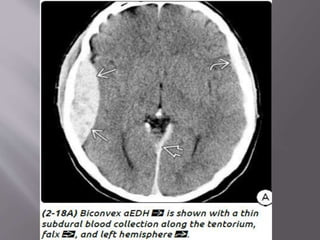

 CT - classic (arterial) EDHs is a hyperdense (60-

90 HU) biconvex extraaxial collection (2-18).

Presence of a hypodense component ("swirl"

sign) is seen in about one-third of cases and

indicates active, rapid bleeding with

unretracted clot.

“Buckling" the gray-white matter interface

b) Venous EDH- smaller, low pressure, develop

slowly

Most venous EDHs are caused by a skull fracture

that crosses a dural venous sinus and therefore

occur in the posterior fossa near the skull base

(transverse/sigmoid sinus) or the vertex of the

brain (superior sagittal sinus).

In contrast to their arterial counterparts, venous

EDHs can "straddle“ intracranial compartments,

crossing both sutures and lines of dural attachment

and compressing or occluding the adjacent venous

sinuses.